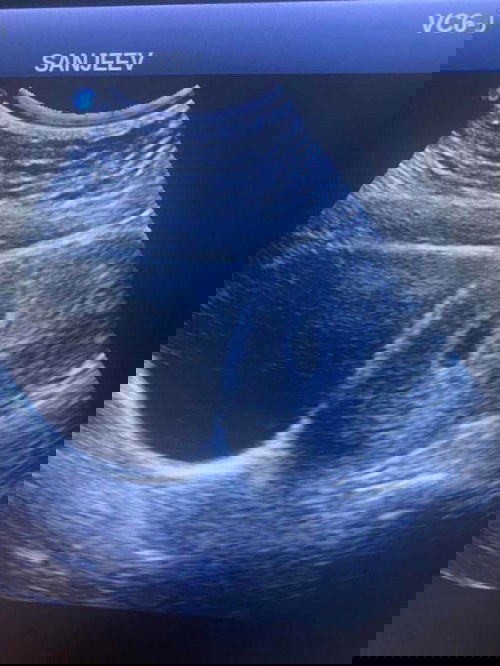

Janin tidak nampak

Assalamualaikum saya mengandung 7 minggu 1 hari . Tadi sya check up tapi belum nampak janin , kantung saja yang membesar dri minggu lalu . Doktor cakap biasanya 7 minggu dah ada janin Dan heartbeat . Nanti scan lagi minggu depan . Sapa kat sini pernah scan 7 minggu tapi kantung saja dan lepas tu next scan dah ada janin ? Saya risau dan sedih sangat . Sepanjang kehamilan tiada bleeding 😔😔😔. #firstbaby #pleasehelp #1stimemom